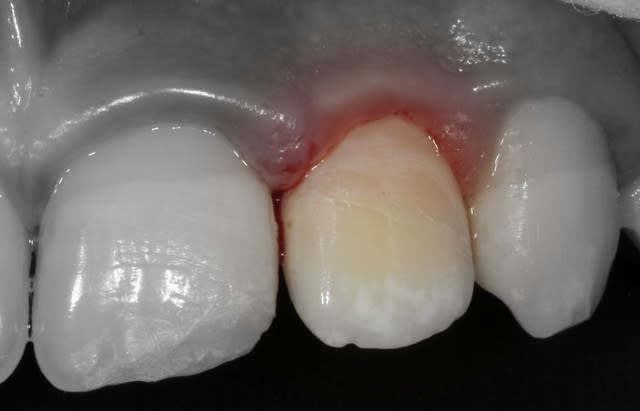

Le fragment fracturé, récupéré par la maman, est collé.

Forcemment, le mimétisme est top.

Pardon je n'avais pas lu. Il n'en reste pas moins que c'est du superbe travail.

- Le collage du fragment coronaire peut se faire même très longtemps après la fracture (plusieurs semaines) : on le conserve dans du sérum physiologique, au frigo, pour éviter un aspect déshydraté.

Mordançage et adhésif sur la dent et sur le fragment. Si le fragment s'adapte parfaitement, l'adhésif est polymérisé quand le fragment est en place. Si l'adaptation n'est pas parfaite (léger hiatus par endroit), je polymérise l'adhésif avant puis utilise du composite fluide entre le fragment et la dent.